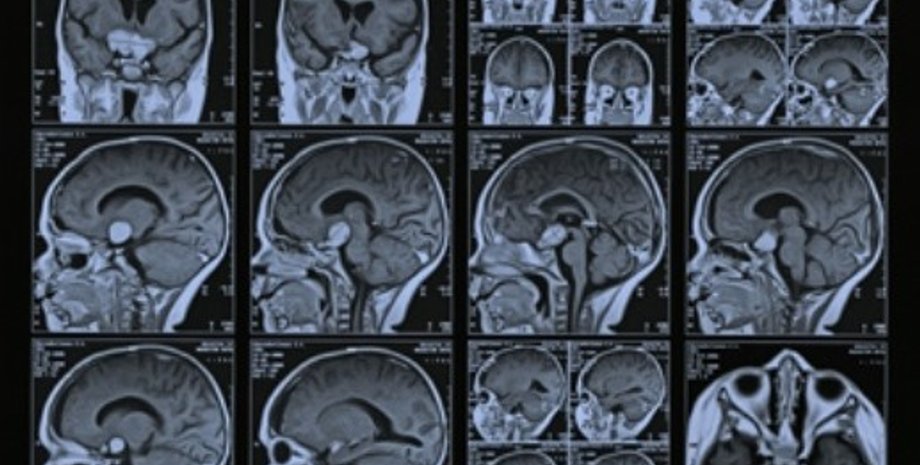

Группа китайских ученых под руководством Хао Лэя из центра магнитно-резонансных исследований в городе Ухань сканировали мозг 17 взрослых людей, у которых была выявлена интернет-зависимость, и сравнили результаты с данными 16 здоровых людей, передает РИА-Новости со ссылкой на Independent.

Чтобы выявить нарушения в мозге у взрослых людей, которые ежедневно проводят много часов в интернете, исследователи использовали магнитно-резонансную томографию. Кроме того, были учтены негативные последствия от многочасового времяпровождения в интернете для личной и общественной жизни.